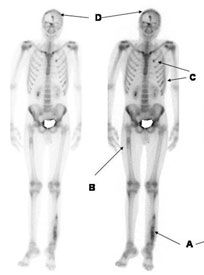

F-18 PET Bone Scans Versus Tc-99m Bone Scans for the Diagnosis of Bone Metastases

PURPOSE:The study will compare 18F-fluoride positron emission tomography (PET) bone scans with traditional 99mTc-methylene diphosphonate (MDP) bone scans. Objectives include determining any significant differences between the 2 tests, and then establishing whether there is a significant change in the clinical management of the bone metastases. The study also will measure and compare any uncertain findings that may have led to additional testing, quantify any adverse effects from either scan, and perform subgroup analyses based on the cancer cell type. Clinical Trials